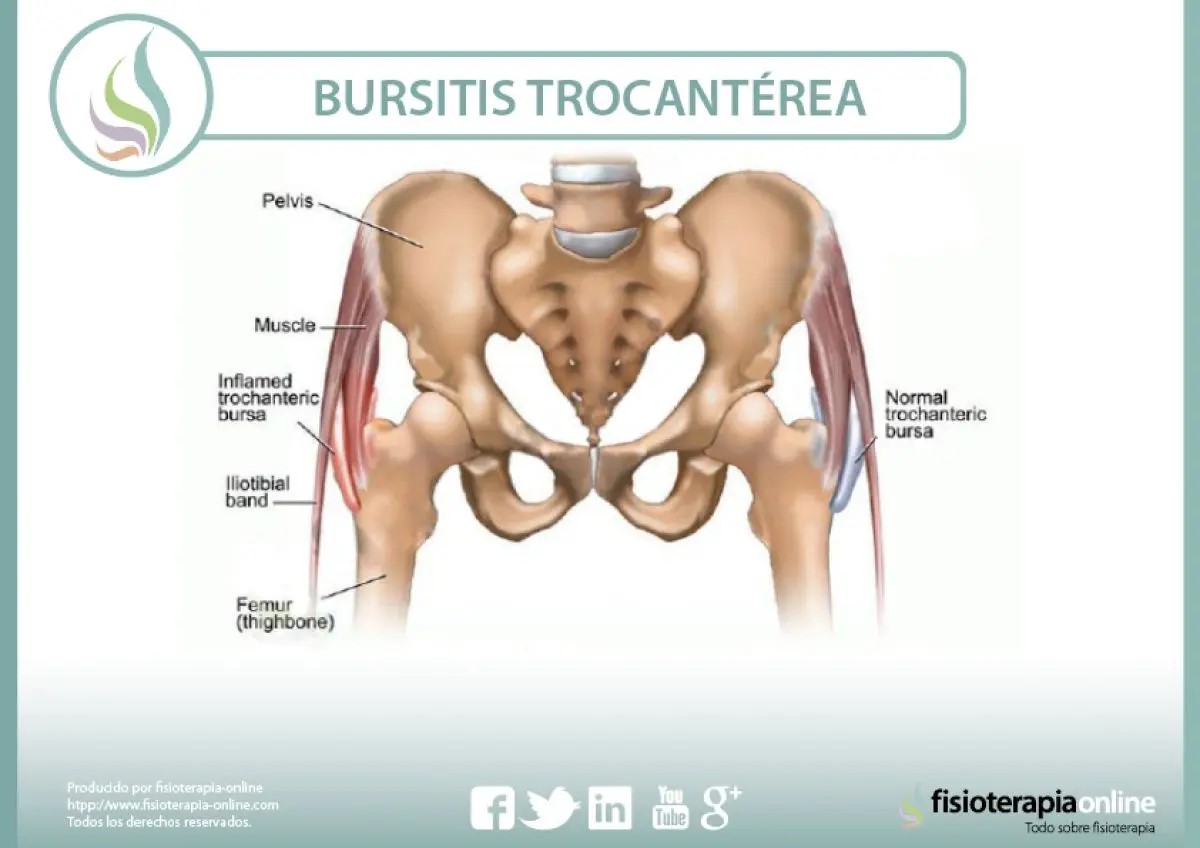

La bursitis trocantérea es una de las patologías típicas de la cadera que afecta la salud, se trata de la inflamación de la bolsa sinovial trocantérea.

Clínicamente esta patología produce posee síntomas de inflamación y dolor en la región glútea y lateral de la cadera, la cual se ve agravada por infinidad de factores como la abducción activa de la cadera, una sedestación prolongada, subir y bajar escaleras y posición de decúbito lateral sobre el lado que se encuentra perjudicado.

Esta patología es causada debido a movimientos repetitivos o posicionales que ejercen presión sobre las bolsas sinoviales de la articulación, otras de las causas también asociadas a esta alteración puede ser lesiones o traumatismos de los músculos o tendones cercanos. Es muy frecuente que está afectación comience sin un claro traumatismo, a través de la acción diaria muscular, generando así microtraumatismos de repetición gracias a la fricción que se produce en el tensor de la fascia lata y la cintilla iliotibial sobre el trocánter mayor y la bolsa sinovial.